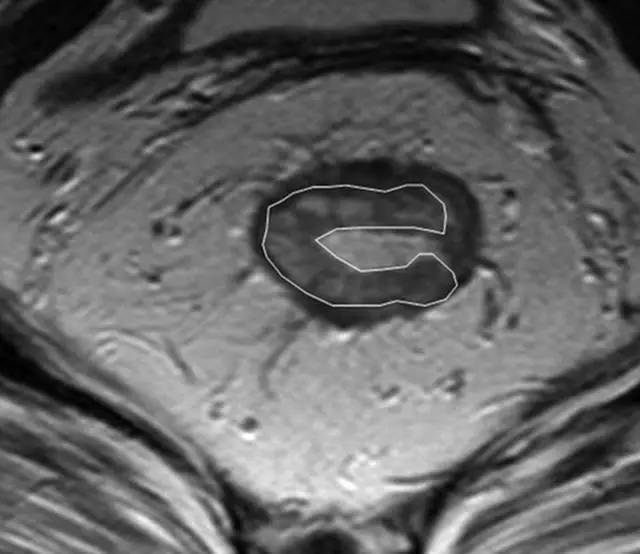

额外看几幅大图:

图片

62 岁直肠癌妇女,薄层 T2 加权轴位 MR 图像显示直肠癌,在 9 点钟位置。

箭头显示直肠系膜筋膜。